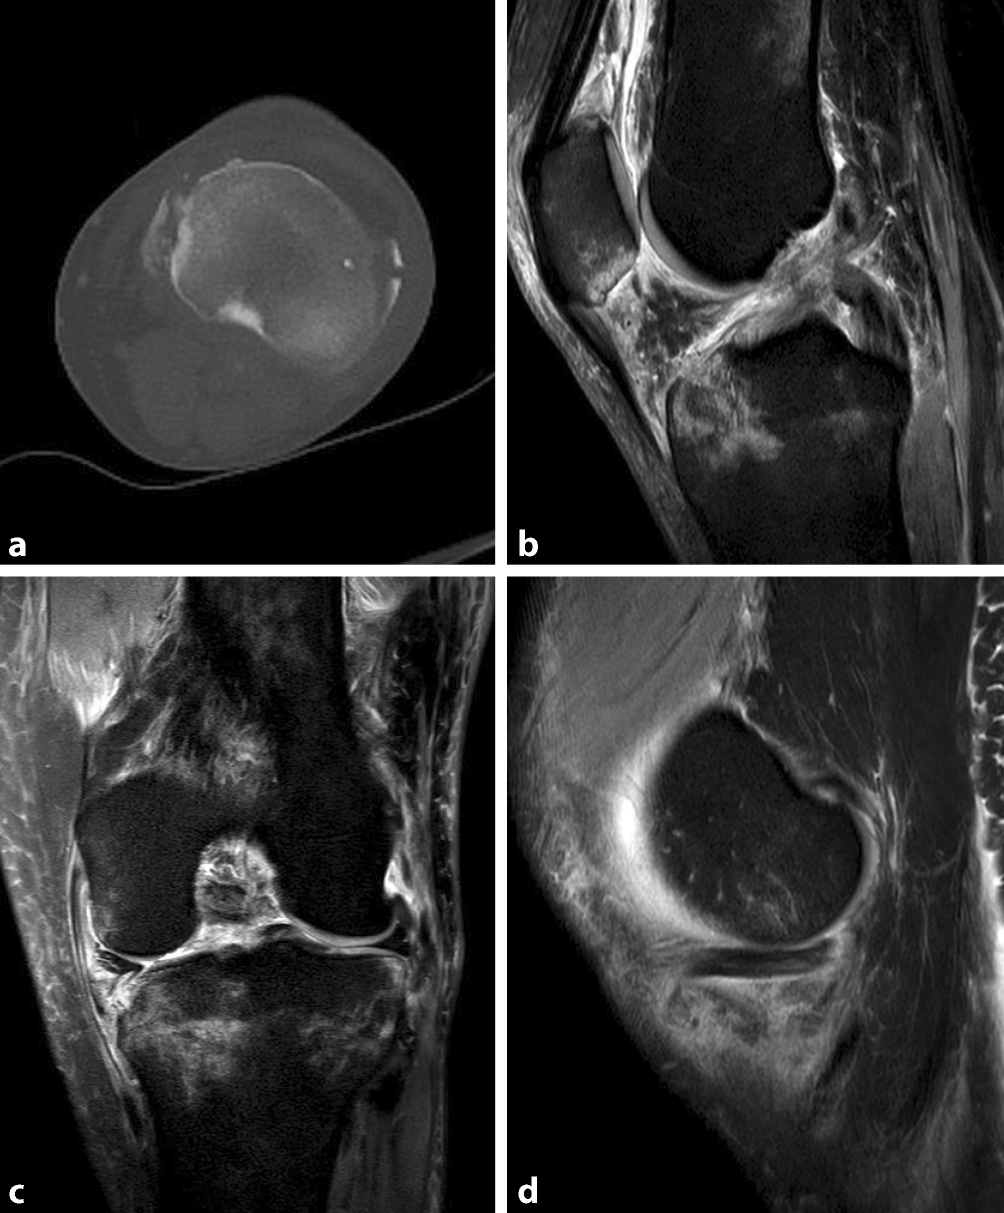

Abb. 4

CT (a) und MRT (bd) einer bikondylären Tibiaplateaufraktur mit begleitender Ruptur des vorderen Kreuzbandes, des lateralen Kollateralbandes sowie Innenmeniskushinterhorns. Fallbeschreibung: 41-jährige Patientin nach erlittenem Hochrasanztrauma mit Zusammenprall als Fußgängerin mit einem PKW mit ca. 80 km/h. Neben einem Schädel-Hirn-Trauma und einer offenen distalen Femurfraktur rechts zeigte sich eine Fraktur des medialen sowie lateralen Tibiaplateaus (a). Aufgrund des Traumamechanismus und des klinisch hochgradigen Verdachts auf weichteilige Begleitverletzungen zeigte eine MRT-Untersuchung eine Ruptur des vorderen Kreuzbandes (b) sowie des lateralen Kollateralbandes (c) und eine nichtdislozierte Ruptur des Innenmeniskushinterhorns (d)

Bild vergrößern